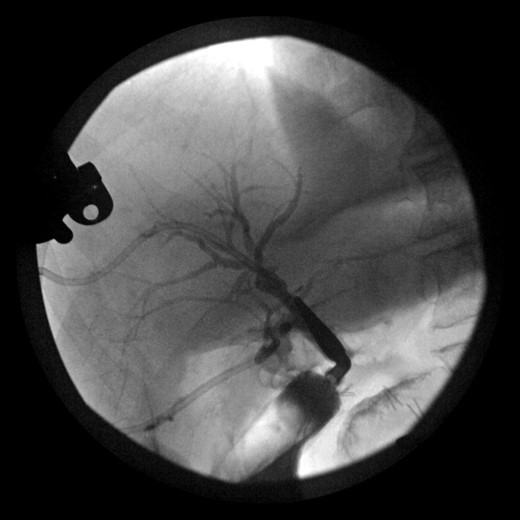

The patient was placed on broad spectrum antibiotics and treated for atrial fibrillation with rapid ventricular response. Laboratory workup revealed a bilirubin level of 17 mg/dl, as well as profound protein–calorie malnutrition with an albumin of 1.9 gm/dl. A percutaneous cholangiogram was performed confirming a hilar ligation of his hepatic duct with inability to pass a wire or catheter distally. A right posterior and right anterior percutaneous cholangiogram catheter was placed for definitive biliary diversion (Fig. 2). The patient was then managed with high calorie, high protein enteral nutrition through a nasogastric Dobhoff tube for approximately 7 days until able to tolerate appropriate oral intake for discharge. He was scheduled for follow-up in 2 weeks.

Cholangiogram of right intrahepatic ducts with abrupt cutoff at surgical clips.